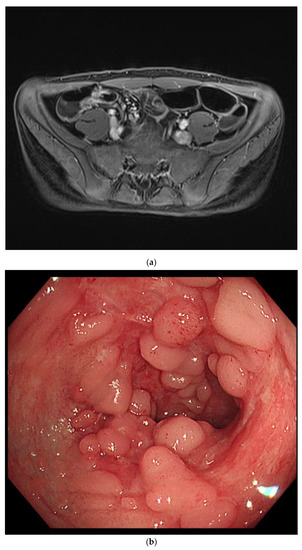

On the second day of hospitalization, he complained of dizziness, chest discomfort, and dyspnea before magnetic resonance (MR) enterography and endoscopy were performed. Vital signs were unstable; blood pressure was 80/60 mmHg, heart rate was 128 beats/min, respiratory rate was 30/min, body temperature was 36.4 °C, and oxygen saturation was 80%. Arterial blood gas analysis revealed a pH of 7.5, pCO2 of 31, and HCO3 of 24.2. Chest radiography and CT revealed pulmonary edema and cardiomegaly (Figure 1).

Figure 1.

Compared with the chest radiography (a) at the time of admission, the chest radiography (b) and low-dose chest computed tomography (c) performed on the second day of hospitalization revealed pulmonary edema and cardiomegaly findings (b).